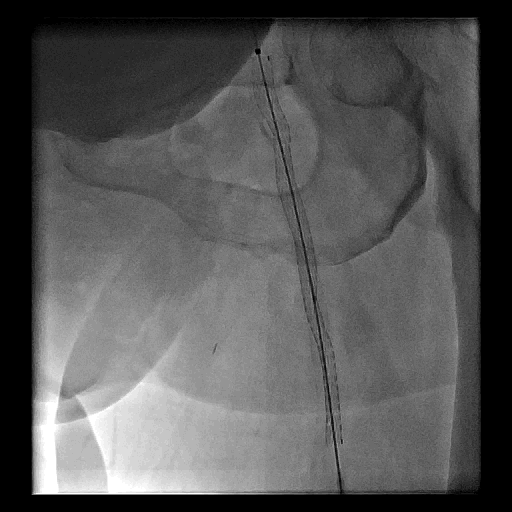

Figure 2.  左小腿血管的經皮腔內血管成形術治療

A. 左側膝蓋下血管多條阻塞

B.經皮腔內血管成形術後,重建多條血管